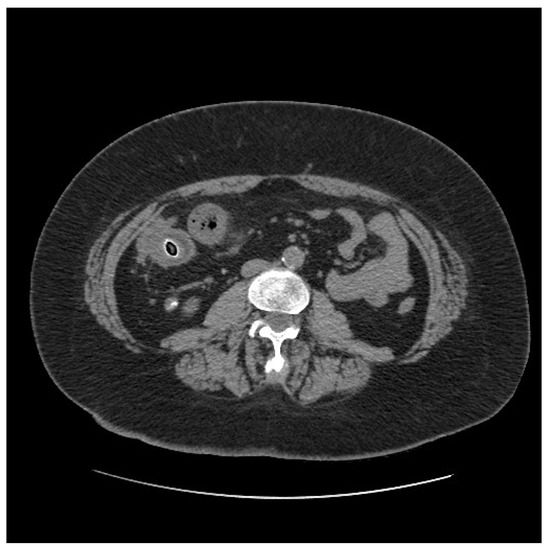

1.2. Case 2